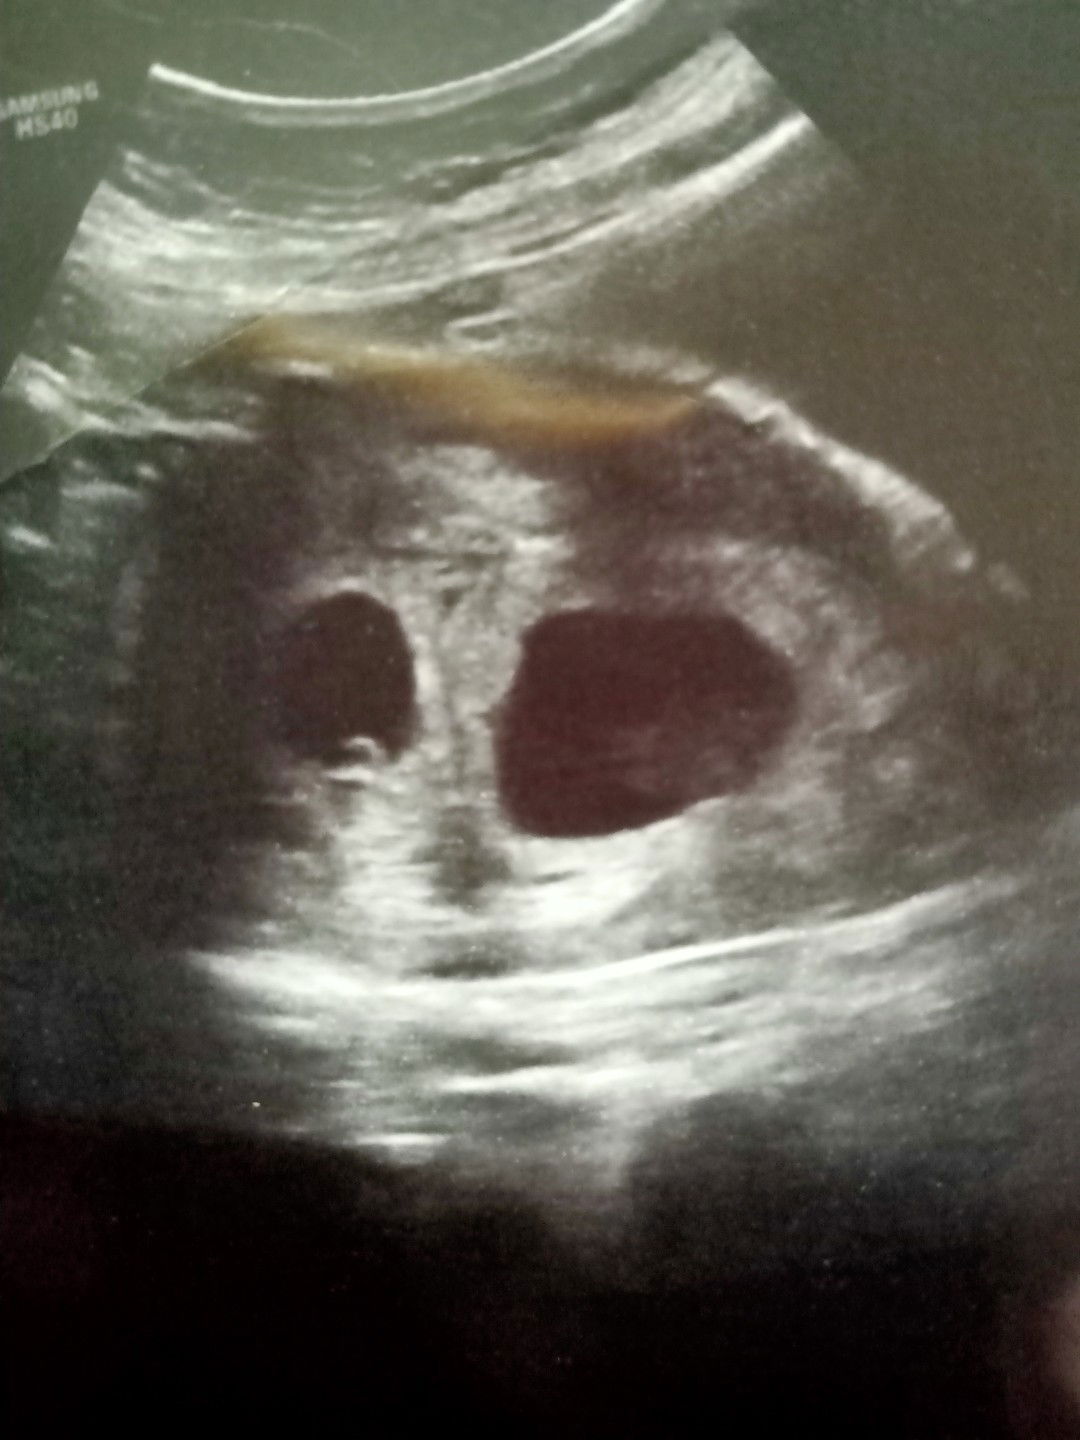

Bulan 2/2020...keguguran.... Bulan 6/2020... +ve pregnant... Saya dan suami sungguh gembira...anak ketiga kandungan keempat.... 1/7/2020..Suami dapat surat MSS(diberhentikan kerja setelah 10 tahun bekerja).. Saya dan suami rasa sangat tertekan....tapi lama kelamaan saya dan suami redha...15/7/2020...kali pertama scan untuk tau perkembangan kandungan....Ya Allah... Doktor kata nampak mcm 2 kantung... Suami mcm nk pitam....rupanya memang ada 2 nyawa didalam kandungan saya.... Bila nampak 2 jantung kecil berdegup.... Sayu rasanya..... Saya dan suami tiada sejarah kembar....rupanya Allah tarik satu rezeki itu sbb Allah nak bagi rezeki lain....Mohon ibu2 tolong doakan kandungan saya sihat selalu...Semoga ibu-ibu semua diberikan kesihatan yang baik dan dipermudahkan segala urusan....